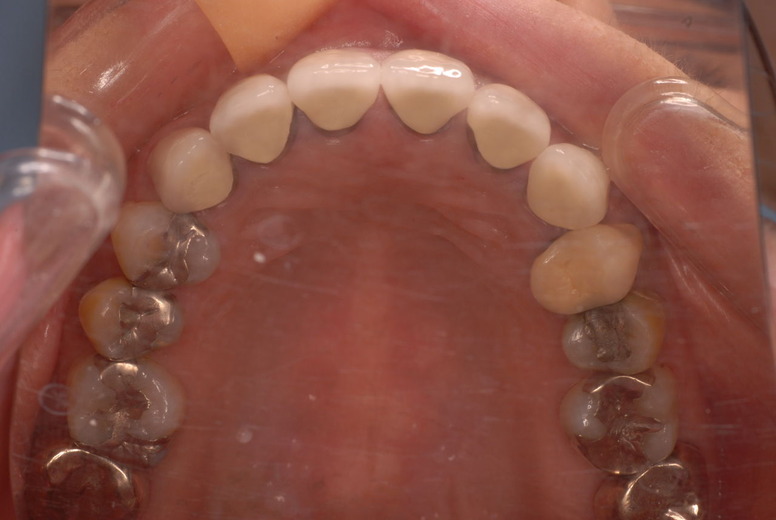

![a7fa4f9f-s[1]](https://livedoor.blogimg.jp/netdental/imgs/a/3/a3950330.jpg)

平成9年治療終了![a535535b-s[1]](https://livedoor.blogimg.jp/netdental/imgs/a/6/a6d0d873.jpg)

平成24年一部欠けて来院

15年前と同じように詰めて終了。磨き方はまあまあでした。でも問題少ないでしょう。![ea7f9628-s[1]](https://livedoor.blogimg.jp/netdental/imgs/c/2/c2ef91be.jpg)